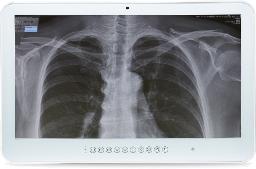

Compliance to DICOM Part 14 可清晰閱讀醫療影像如X光片

DICOM是人眼所看到的實際亮度,在電腦螢幕上用明顯的灰階呈現出來,讓X光片的顯影能夠更清晰。Wincomm提供的DICOM功能,設計概念以方便操呈現作為出發點,並提供三種色溫,符合不同地區的喜好選擇。此外特別設計亮度鎖定功能,以保證DICOM模式下,亮度的準確性。

Picture: General screen VS DICOM

醫療用電腦螢幕分為四大類,Wincomm所提供的DICOM屬於Clinical Display,給使用者一個高品質、穩定、精準的醫療顯示解決方案,用來判讀如X光片等醫療影像。